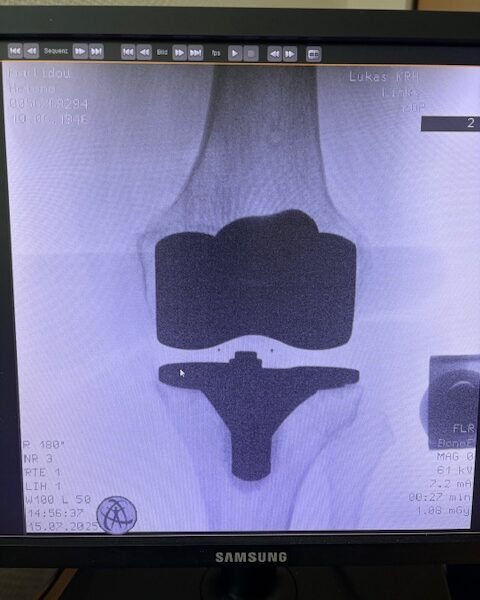

Τα εμφυτεύματα που χρησιμοποιήθηκαν στο γόνατο της ασθενούς είναι της Aesculap: E-Motion Pro, μηριαίο μέγεθος 4, κνημιαίο μέγεθος 4, με ενθέμα (inlay) 10mm.

Ήδη από τις πρώτες εβδομάδες, περπατούσε χωρίς πόνο, με βελτιωμένο εύρος κίνησης.   Η παθητική κίνηση κατα την έξοδο της ασθενούς από την κλινική ήταν E/F : 0-0-120 Επίσης πλήρη σταθερότητα του γόνατος σε κάμψη και έκταση.